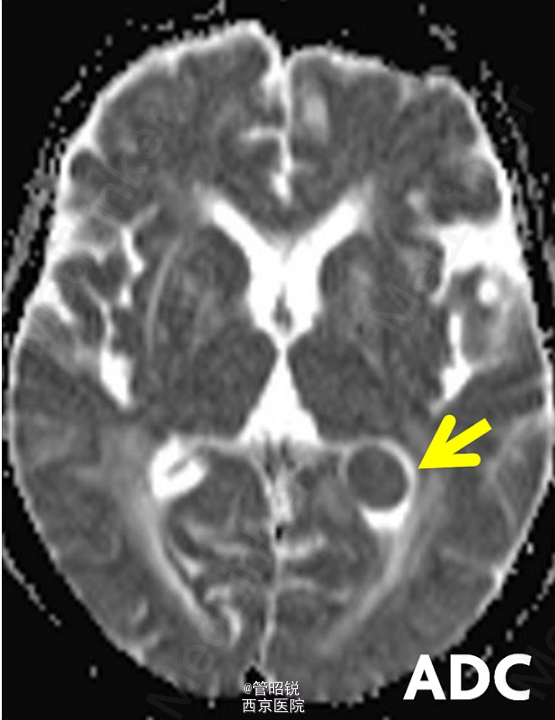

脑室内脑膜瘤占脑膜瘤的0.5%-3%,主要分布在三角区。常发生于中老年女性。原始瘤细胞被认为起源于蛛网膜帽细胞,常常表现为交感神经异常的相关症状,或者症状多变。经典的影像学结果包括CT高密度团块、T2孤立的低信号影、T1WI强化后显示均匀增强。需同转移瘤、淋巴瘤和囊虫病相鉴别。来源于AJNR